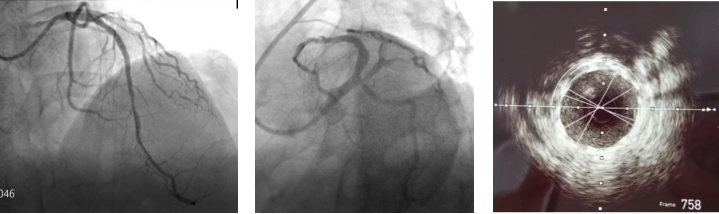

在楚天舒主任指导下,团队顺利使用Shockwave IVL震波球囊对钙化病变处进行多个周期的冲击波治疗。治疗中可见冲击波球囊逐渐扩张开顽固钙化区域,冲击波治疗后复查造影可见左前降支近中段的钙化狭窄处明显改善。术中植入的2枚药物洗脱支架在行IVUS中可见支架贴壁和膨胀良好,血管扩张成形满意。术中患者无明显不适,未见低血压、ST改变及心律失常,术后患者胸痛症状明显好转。目前,该患者病情平稳,胸痛症状完全缓解。

术后造影

Shockwave IVL相比传统的“冠脉内旋磨”技术具有血管损伤并发症少,能处理偏心钙化、优化支架释放等优点。目前我院已配备2间DSA导管室,具备OCT、IVUS、FFR、冠状动脉内高速旋磨、ECMO、IABP等众多先进仪器设备。在与时俱进的治疗观念下,运用先进仪器设备,我院心血管内科成功挽救了众多急危重症患者的生命。今后心血管内科二病区将继续开拓进取,不断前行,为更多重症患者的生命健康保驾护航。